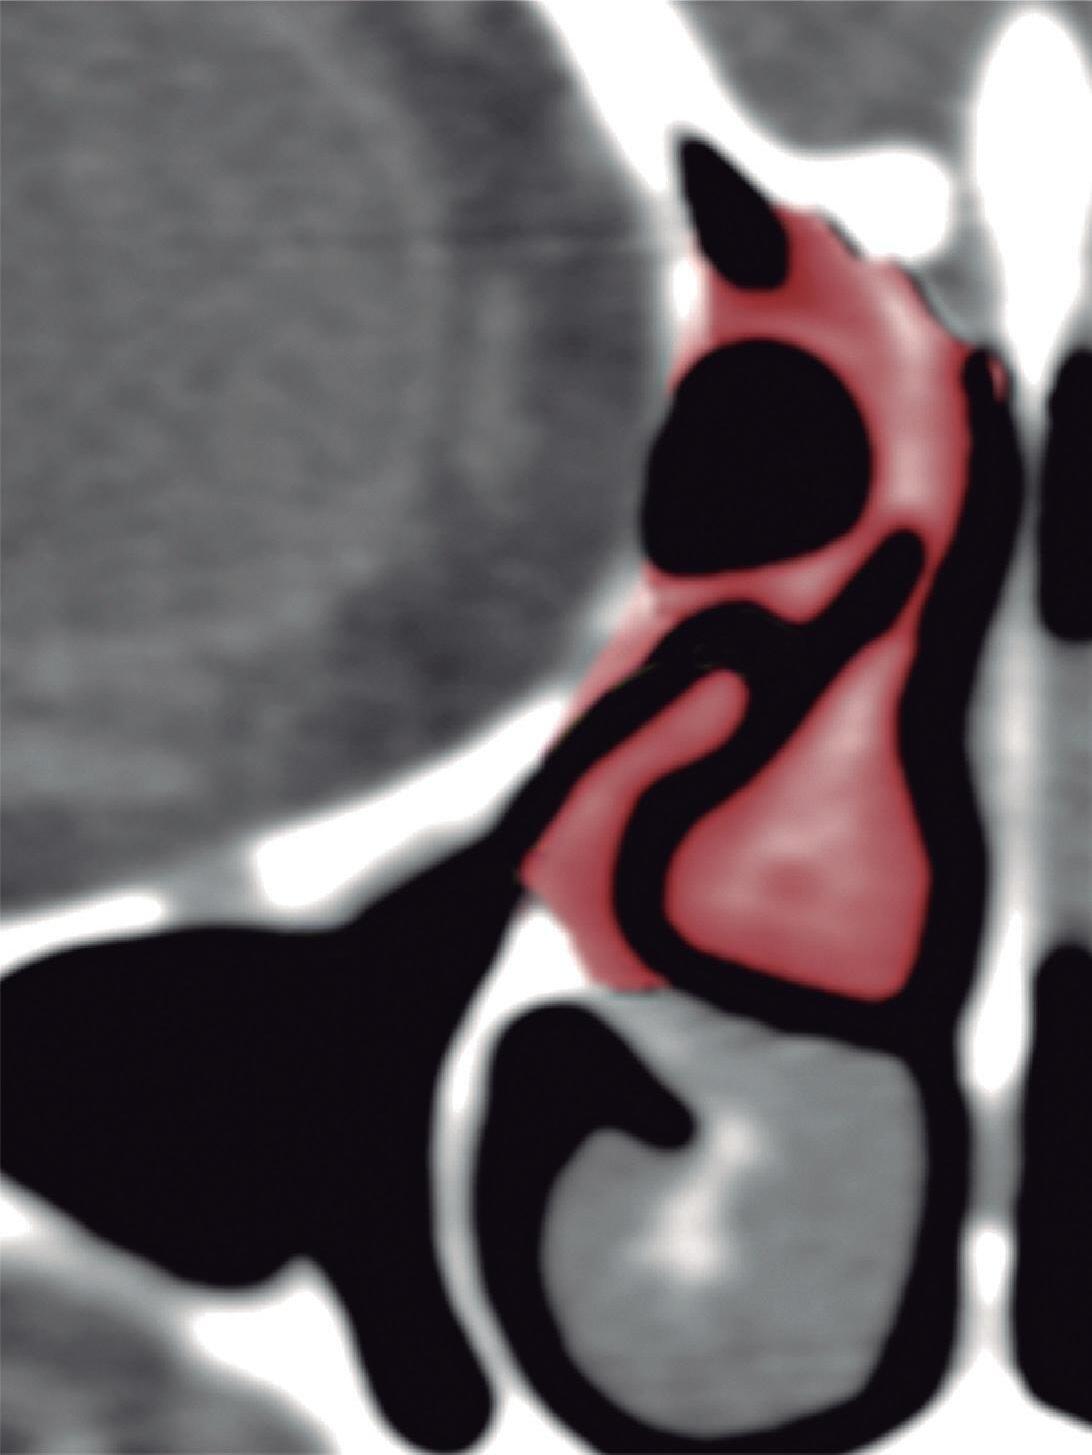

1-4. TC e reconstrução 3D com destaque para estrutura etmoidal (em vermelho), funcionando como câmaras de baixa pressão para drenagem do seio maxilar.

1-7. TC com reconstrução 3D mostrando em vermelho apenas o seio etmoidal e não o osso etmoidal, e sua relação com a fossa nasal, o seio maxilar, órbita e fossa anterior.

Este complexo anatômico chamado seio etmoidal, controla a pressão e o fluxo aéreo que penetra nos verdadeiros seios paranasais e pode ser interpretado como um sistema de câmaras aerodinâmicas de baixa pressão cuja topografia particular faz dele o centro anatomofuncional do aparelho rinossinusal.

Na estrutura do seio etmoidal as câmaras aerodinâmicas denominadas meatos, oferecem um espaço fisiológico definido para os seios esfenoidal, maxilar e frontal e são dispostas arquitetonicamente para impedir que o fluxo inspiratório (rápido, frio e seco) penetre nestas cavidades, e permitir a entrada do fluxo expiratório (lento, aquecido e úmido). Existem pelo menos duas e as vezes três câmaras etmoidais na parede lateral do nariz que são os meatos, médio, superior e supremo.